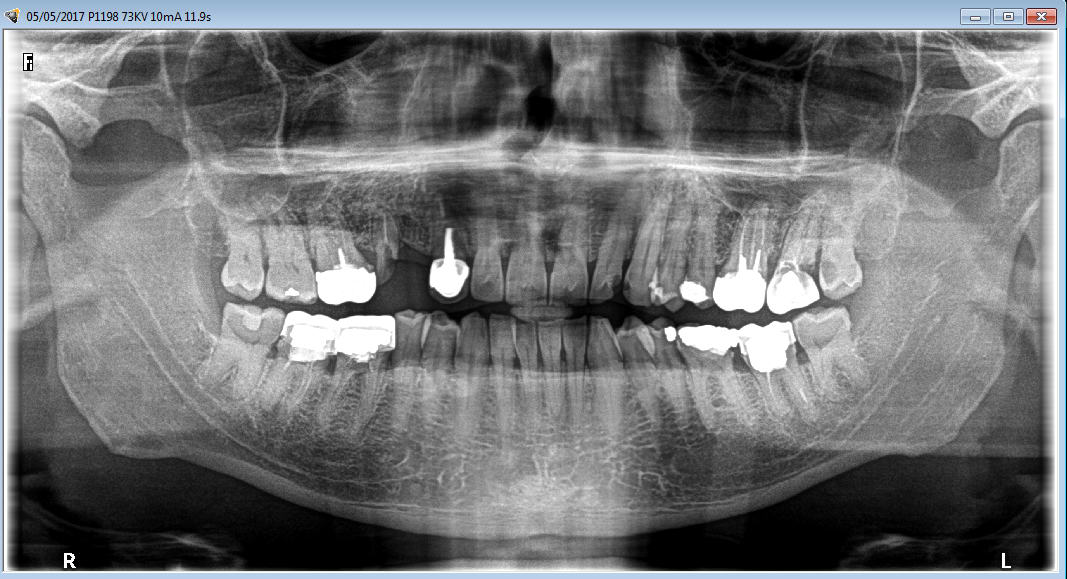

un confrère a pris sa retraite , je soigne les parents, et j'herite de ça sur un patient de 43 ans

moi une patate comme celle qu'il y a au dessus de la 22 j'en ai vu 3 ou 4 en 40 ans

On voit rien sur ton pano. -)

Belle patate aussi sur dent intacte. -)

en fait lésion sur 22 de la taille d'une clémentine corse

interessant à la fois le sinus et les fosses nasales

j'avais déjà vu des grosses patates mais plutôt étalées latéralement

une qui se developpe si haut jamais )

c'est tellement monstrueux que je me demande à qui l'adresser

moi aussi les panos de merde c'est tous les jours

mais un patient laisse avec une lésion si monstrueuse , grace au ciel , c'est seulement tous les 10 ans

Je crois qu'aucun de nos confrères n'avait vu la lésion sur 22...

Vous pouvez cependant apprécier l'endo locale :)